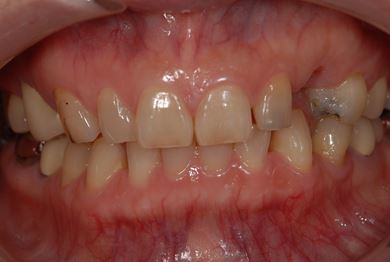

インプラントの症例写真 IMPLANT

インプラント治療

| 主訴 | 乳歯がぐらついている。 | ||||||||||||||||||||||||||||||||

| 治療方針 | インプラント治療にて、機能的・審美的回復を行う。 | ||||||||||||||||||||||||||||||||

| 治療内容 | インプラント1本、メタルボンドセラミッククラウン1本 | ||||||||||||||||||||||||||||||||